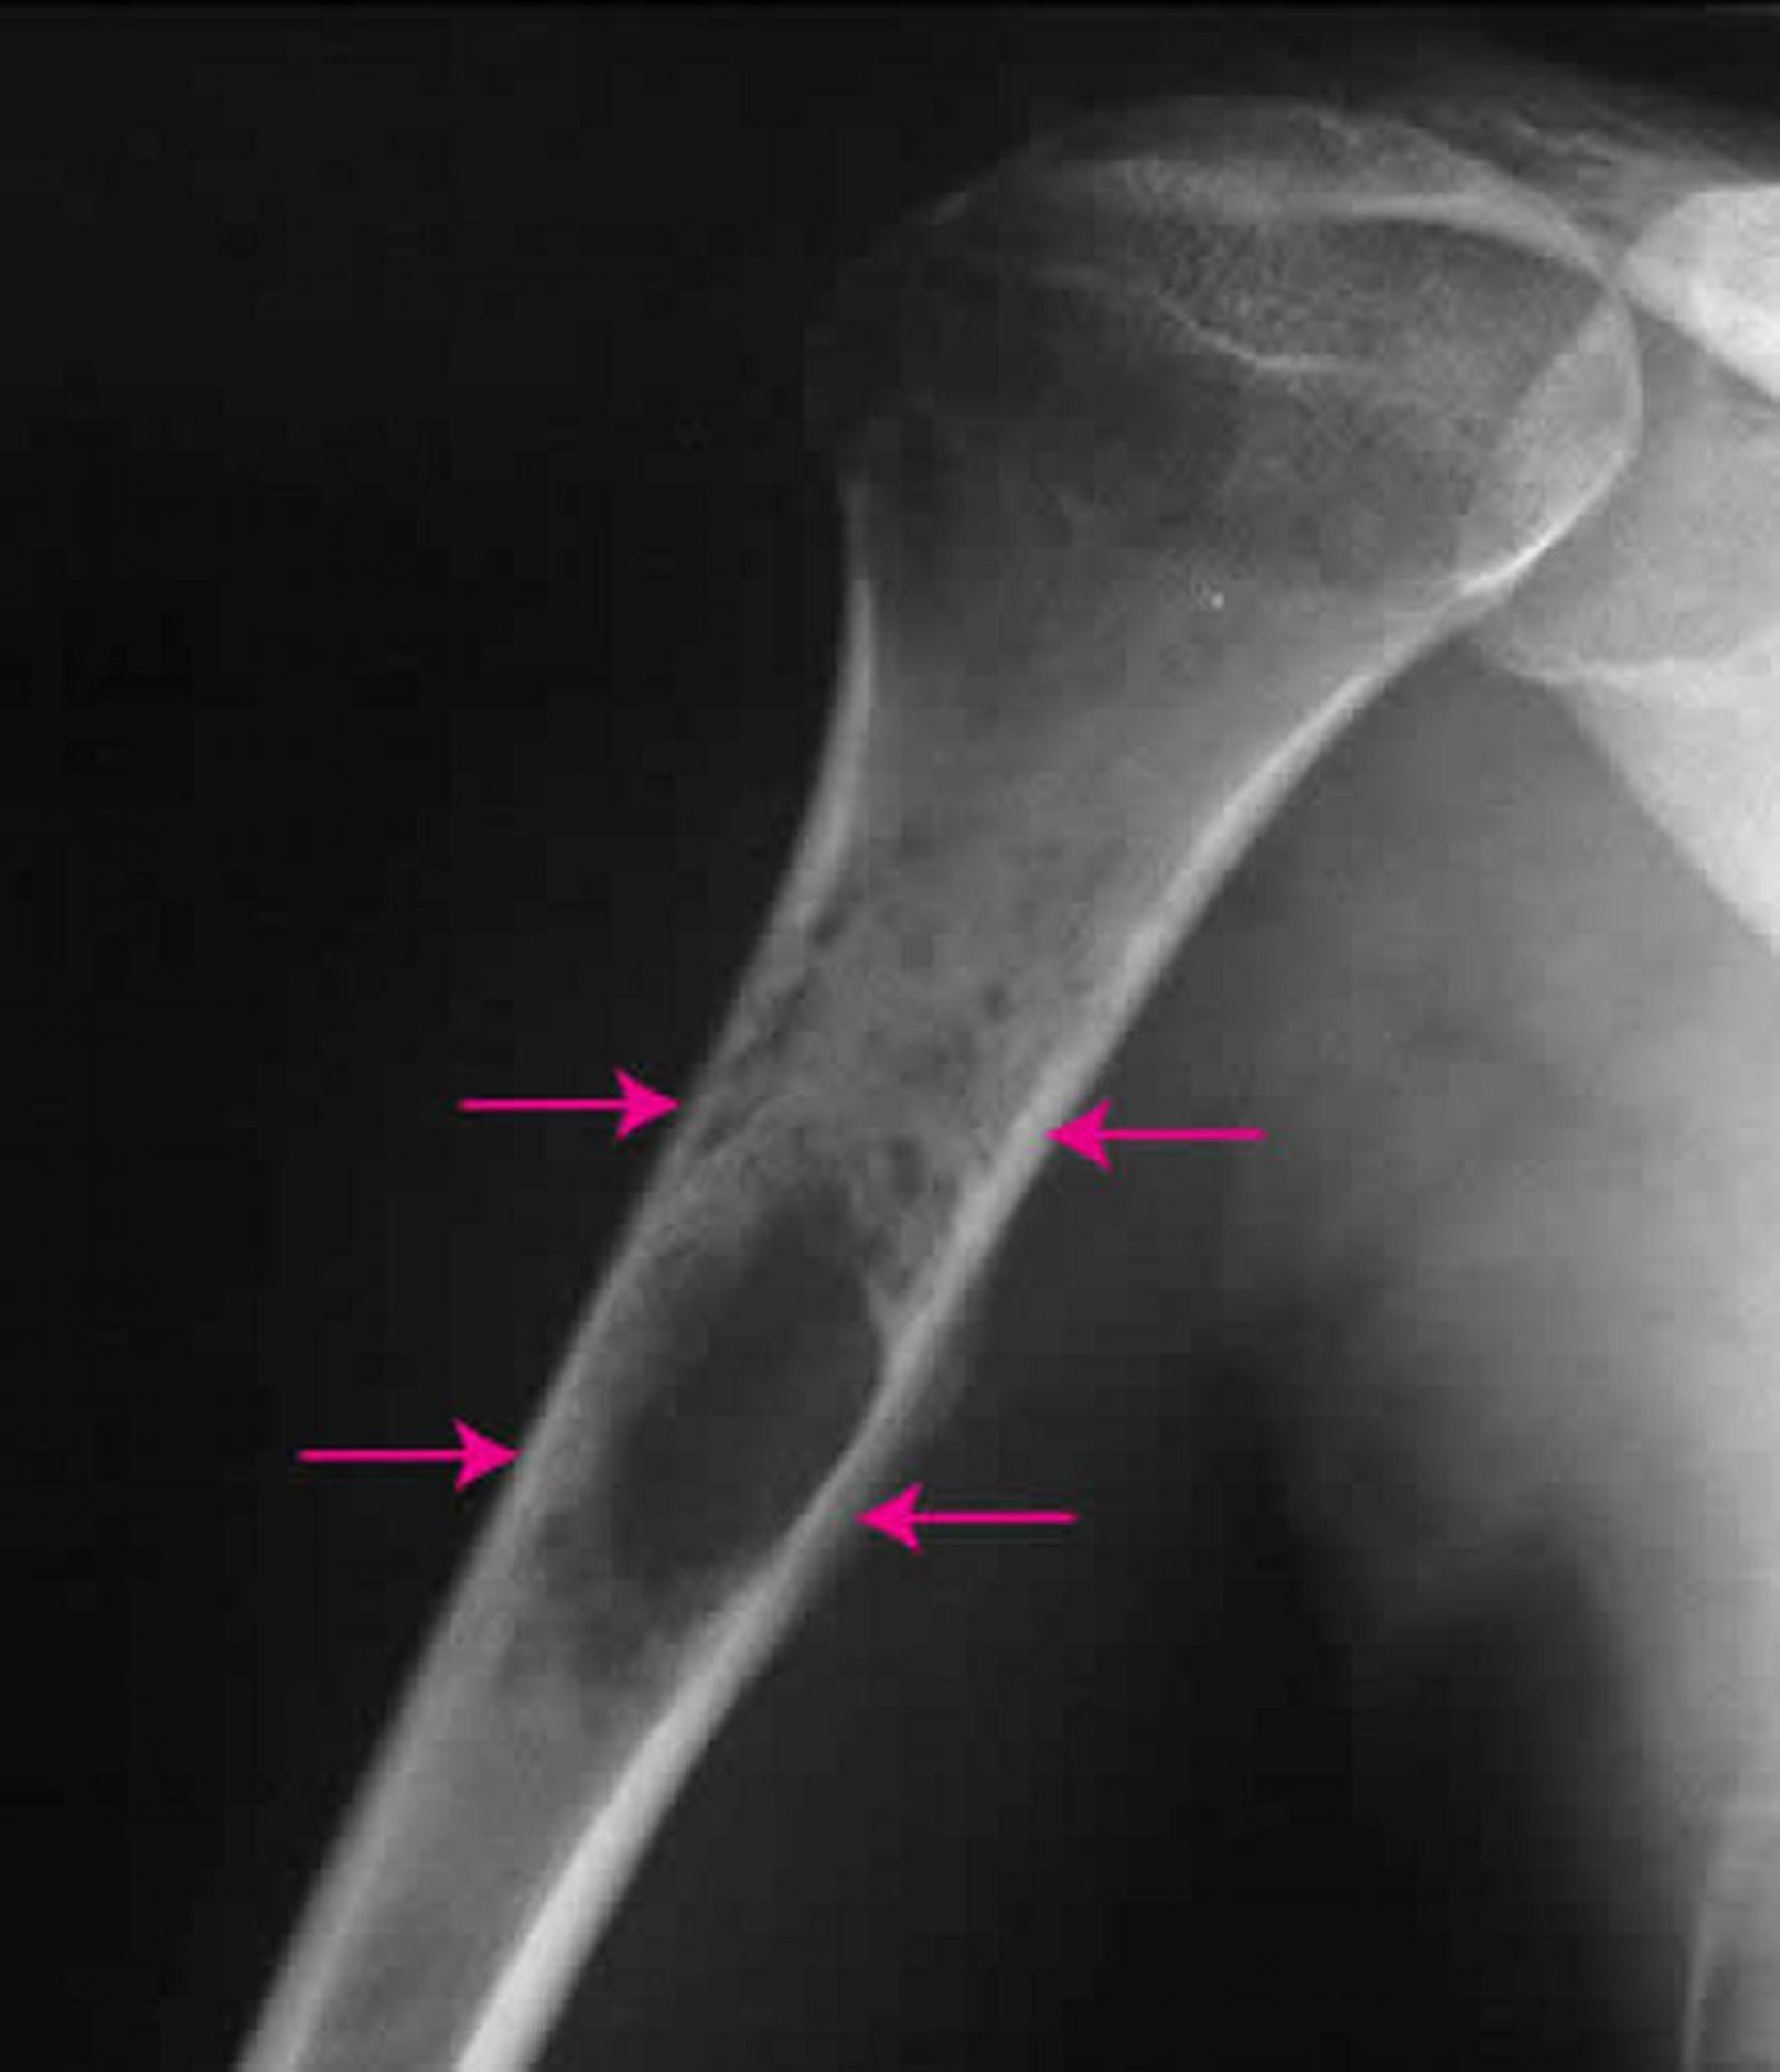

Ewing-Sarkom im Knochen

Auf dieser Röntgenaufnahme einer Schulter ist ein Ewing-Sarkom (Pfeile) im Oberarmknochen zu sehen.

Bild mit freundlicher Genehmigung von Dr. med. Michael J. Joyce und Dr. med. Hakan Ilaslan.